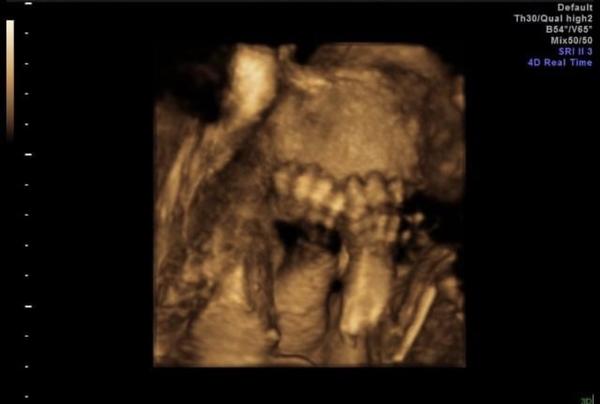

Dcerka měla celou dobu připláclou nohu na čele a nehlo s ní vůbec nic. Byla velký spáč a nevzbudila se, aby změnila polohu.